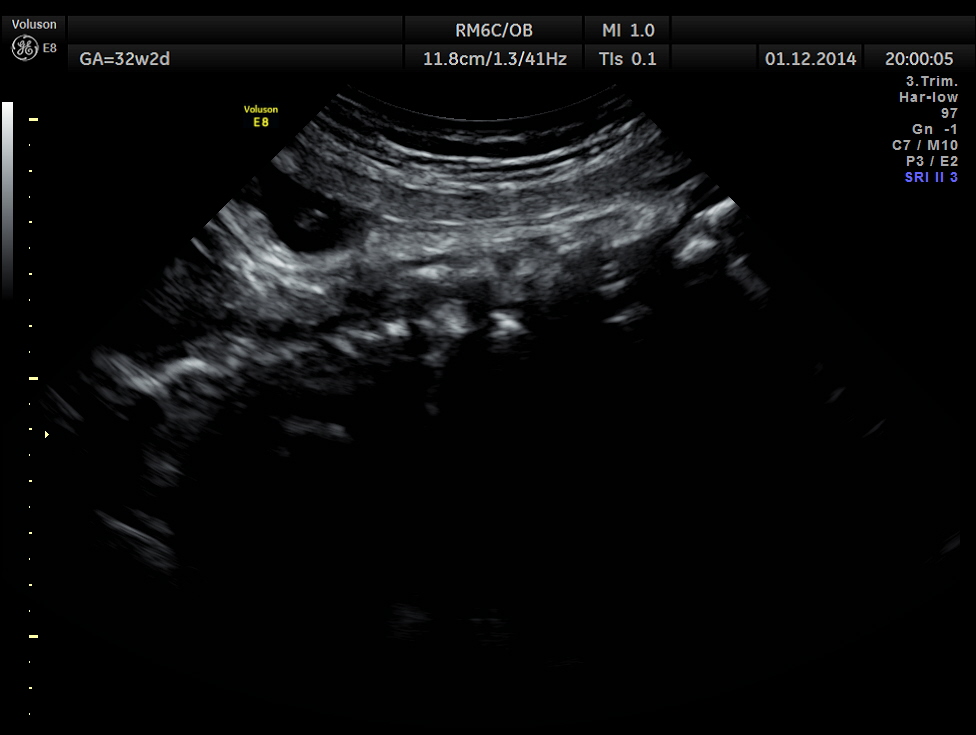

This was a 30 year old lady , with history of consanguinity ; 2nd gravida , 1st child normal ; she has never gone for an ultrasound examination in this pregnancy and was sent by her consultant to a different centre for evaluation . She was found to have hydrocephalus and was referred to our clinic for 2nd opinion.

The following images were obtained.

Careful examination revealed a neural tube defect with meningo myelocele at the lumbo sacral level.

Spinal deformity was also noted.